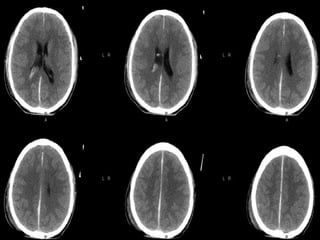

SUBDURAL HEMATOMASUBDURAL HEMATOMA Occursbetween the dura and arachnoid Can cross the sutures but not the dural reflections Due to disruption of the bridging cortical veins Hypodense(hyperacute, chronic), isodense(subacute), hyperdense(acute)

• 12.